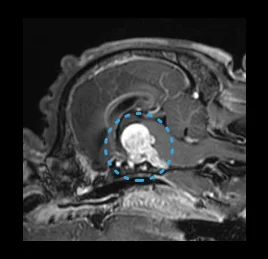

• 뇌하수체 종양